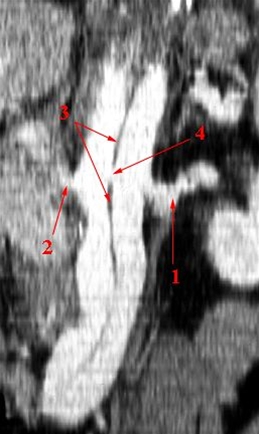

Nederste billede er et længdesnit (coronal rekonstruktion).

- Venstre nyrearterie perfunderes fra det sande lumen

- Højre nyrearterie perfunderes fra det falske lumen

- Aortalumen er delt i to af den løsnede intima, der står som en membran mellem det sande og det falske lumen

- Hul i intima (re-entry) i niveau med nyrearterierne